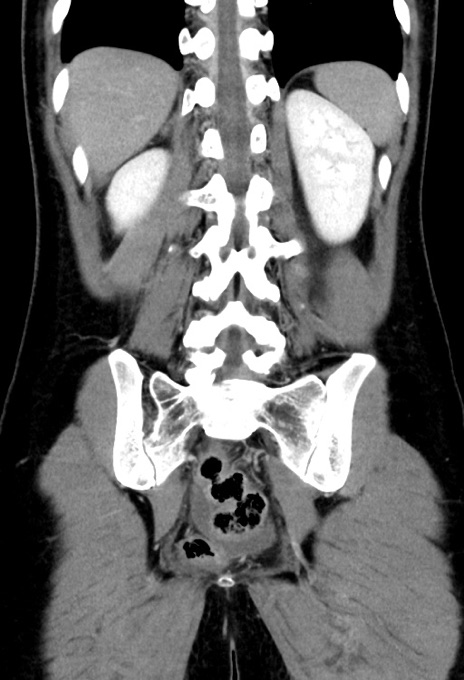

症例17(冠状断像)

【症例】20歳代女性

【主訴】嘔吐、下腹部痛

【現病歴】昨日夕食後に嘔吐し下腹部痛が出現。本日になっても嘔吐持続し改善しないため来院。

【身体所見】意識清明、BT 37.2℃、BP 108/67mmHg、腹部:平坦、やや硬、下腹部正中から右にかけて圧痛あり、反跳痛軽度あり、tapping pain(+)。

【データ】WBC 13600、CRP 14.94